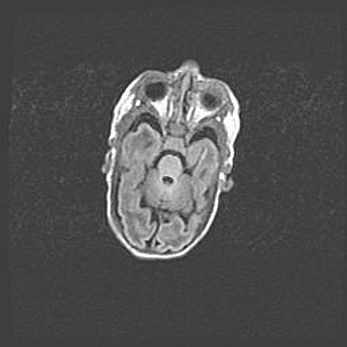

Множественные кисты обоих полушарий головного мозга, наибольшая из них в правой затылочной области. Ассиметричная атрофическая гидроцефалия.

Возраст: 7 месяцев

Вес: 5660 г

Пол: мужской

Окружность головы: 41,5 см

Срок гестации: 28-29 недель

Кисты головного мозга развиваются в результате многоочаговых некрозов вещества мозга и возникают вследствие перенесенной перинатальной инфекции, менингитов, энцефалитов, асфиксии, родовой травмы, расстройств мозгового кровообращения различного генеза. Образованию кист в веществе головного мозга плодов и новорожденных способствуют такие факторы, как высокое содержание в нем воды, недостаточная (или отсутствие) миелинизация и слабая астроглиальная реакция на повреждение.

Кисты могут сочетаться с гидроцефалией и другими поражениями головного мозга.